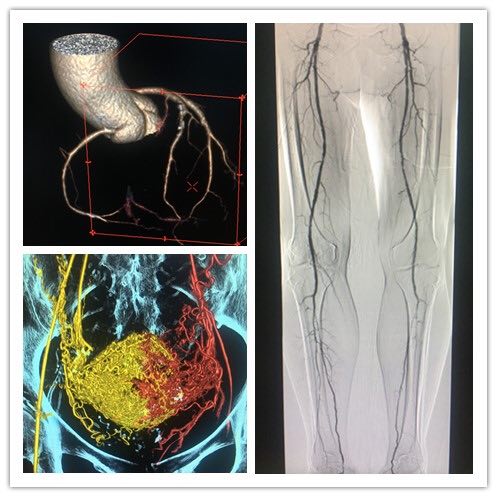

它智能高端!GE IGS系列為GE血管機最新版本,軟硬件均較上一代產(chǎn)品有越級的提升。智能導航技術(shù),Revolution降噪技術(shù),智能混合路徑圖技術(shù),支架增強顯示及高級去導絲減影模式,下肢血管跟蹤造影技術(shù)等等這些只是它的基本功能,3D成像后處理,多圖像融合技術(shù),斷面重建更是讓它在同級別產(chǎn)品中脫穎而出。

(部分功能圖像展示)